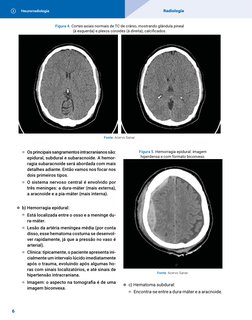

Neurorradiologia Radiologia

Figura 4. Cortes axiais normais de TC de crânio, mostrando glândula pineal

(à esquerda) e plexos coroides (à direita), calcificados.

Fonte: Acervo Sanar.

W Os principais sangramentos intracranianos são: Figura 5. Hemorragia epidural: imagem

epidural, subdural e subaracnoide. A hemor- hiperdensa e com formato biconvexo.

DICA

1. TRAUMA CRANIOENCEFÁLICO Lembre-se de que, em um exame

normal, os plexos coroides e a pineal apa-

recem hiperatenuantes, pois são calcifi-

u a) TC de crânio sem contraste: primeiro exame cados. Então não confunda com sangra-

a ser pedido no contexto de TCE. mento!